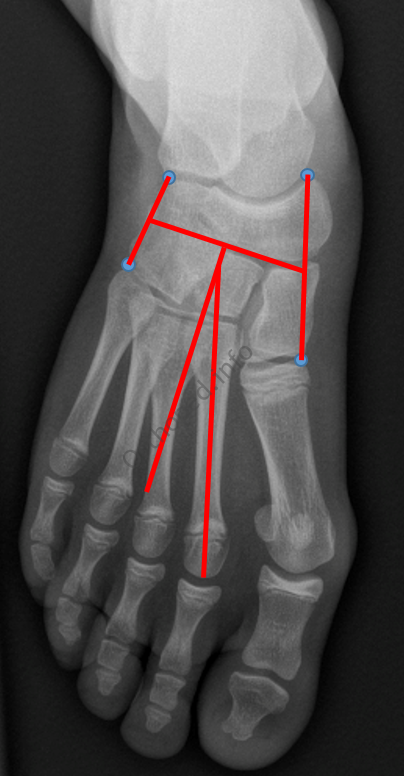

Metatarsus Adductus

- Angle entre le tarse et le métatarse

- Axe du tarse : on relie le point le plus médial de l’articulation talo-naviculaire et le point le plus médial de l’articulation cunéo-M1et on prend le point situé au milieu. On relie le point le plus latéral de l’articulation calcanéo-cuboïdienne et le point le plus latéral de l’articulation cunéo-M5 et on prend le point situé au milieu. On relie ces 2 points et la perpendiculaire à cette ligne détermine l’axe du tarse

- Axe du métatarse : axe du 2è métatarsien

- Normal : 20° (l’axe métatarsien est médial à l’axe tarsien)